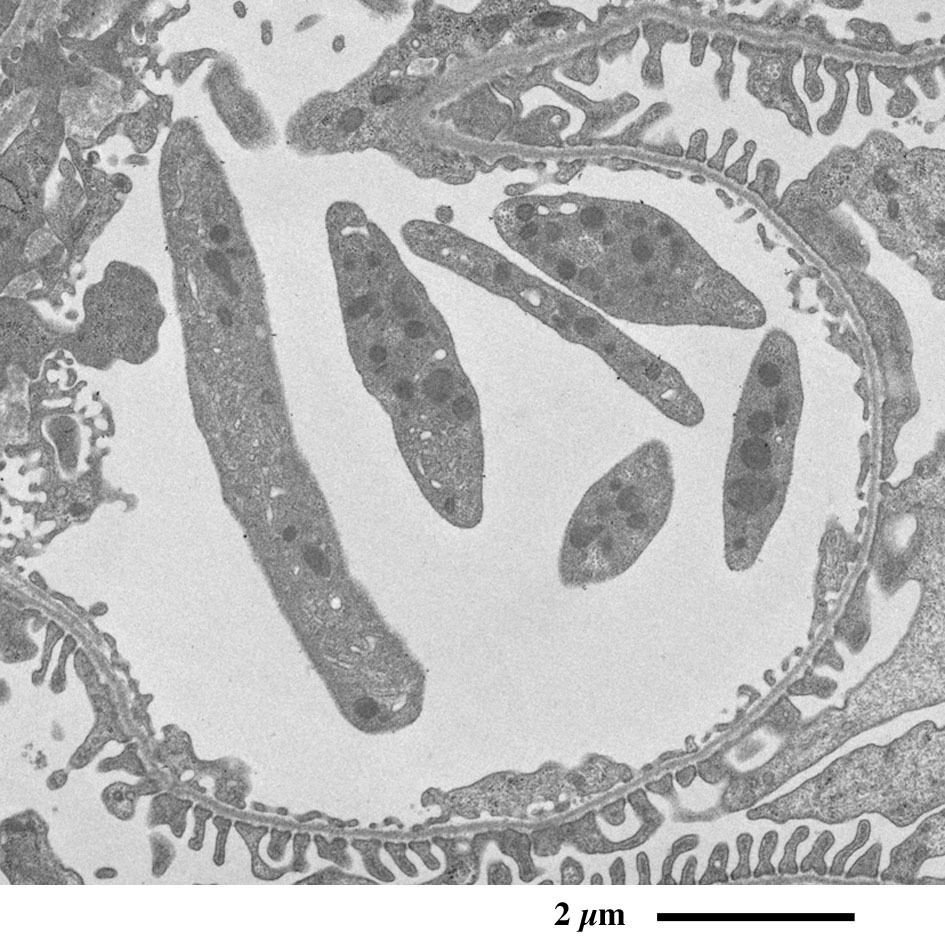

【 超薄切片の透過型電子顕微鏡画像 】

Transmission electron microscopic image of ultrathin section

近位尿細管上皮細胞

(微絨毛横断面)